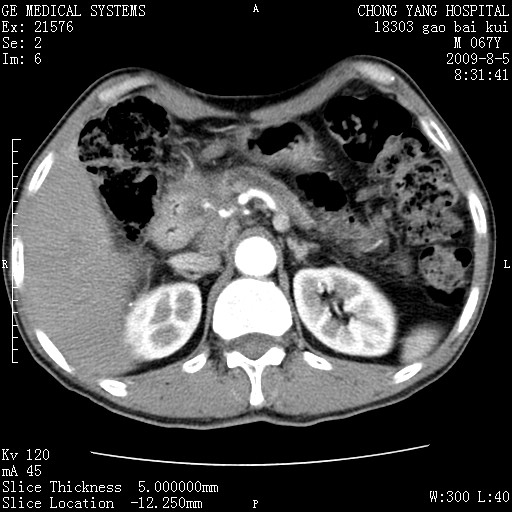

这个也过了,考虑胰腺钩突癌或壶腹癌,不除外胰管粘液乳头瘤伴胰管扩张,肝内胆管积气.

1)考虑胰头癌或壶腹癌并胰管扩张。2)肝外胆管扩张、积气,胆囊影未见;考虑术后改变。3)胃壁增厚?建议必要时行胃镜检查。

虑胰腺钩突癌或壶腹癌,不除外胰管粘液乳头瘤伴胰管扩张,肝内胆管积气.

考虑胰头癌并十二指肠受侵。